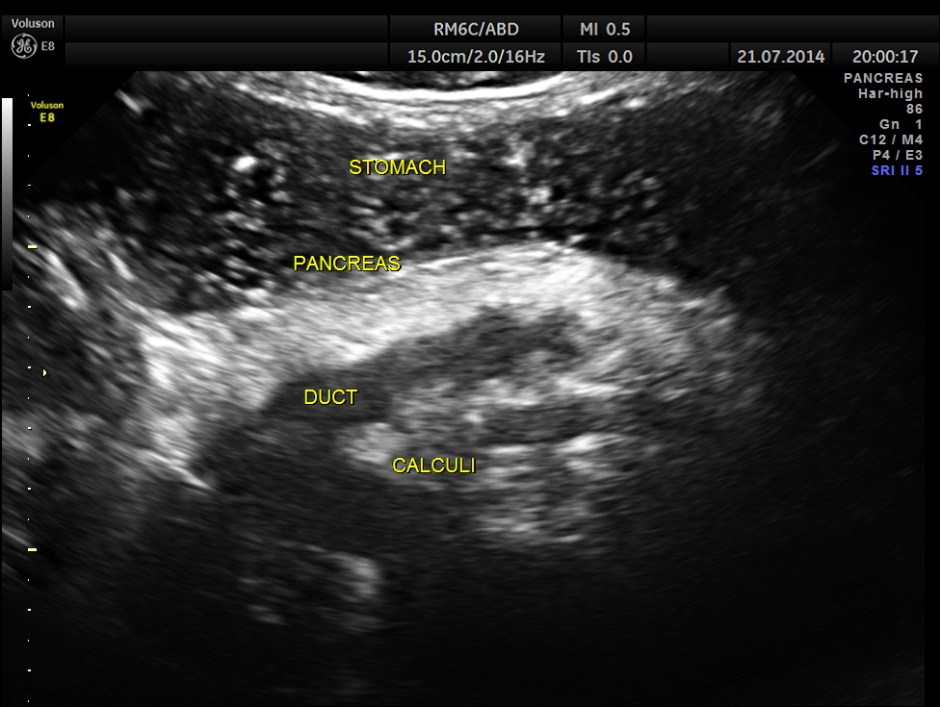

The following pictures show the pancreas.

Pancreatic duct is dilated prominently.

Pancreatic duct dilated.- 12.9 mms.

Pancreatic calculi are seen.